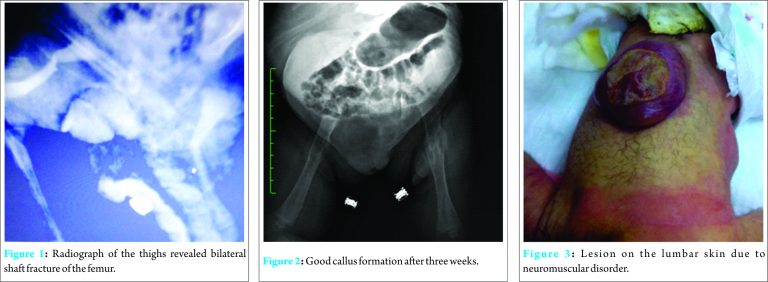

A healthy 18-year-old woman and thirty-nine-week pregnant woman suffered sudden onset of severe pain and was admitted to the obstetrics clinic. Myelomeningocele and breech presentation was previously diagnosed in fetus. In the ultrasonographic (USG) examination; fetal stress and hydrocephaly were determined and urgent cesarean was planned. A 2690 g. female baby was delivered with Apgar scores between seven to eight at an hour and five minutes. Swelling was determined on both her thighs in routine neonatal evaluation few minutes after the delivery. The neonate seemed irritated with the palpation of thighs. She was consulted to our department immediately. Anteroposterior and lateral radiographs of each femur were taken which revealed displaced femur shaft fractures on both sides (Fig.1). At first a pelvipedal cast was thought, however to avoid the lesion irritation on the lumbar skin, long leg splints were performed on both lower limbs for three weeks. The fractures healed uneventfully after three weeks (Fig. 2). The follow-ups were continued at obstetric clinic during hospitalization. Myelomeningocele was repaired by plastic surgeons and neuro-surgeons ten days after her discharge from obstetric department.

Recently, obstetricians take precautions against undesirable complications. The risk of mortality and morbidity has been significantly reduced with C/S performed by accurate techniques and gentle obstetrical maneuvers [6]. Giampiero et al. defined some rules to prevent this complication as; adequate analgesia, extraction by exercising gentle traction, sufficiently wide incision of skin and uterus to allow for a smooth extraction [7]. Nevertheless, the birth trauma risks have been ongoing especially in deliveries with fetal anomalies despite these prevention efforts. The increasing incidence of the fracture due to birth trauma is considered as fetal osteoporosis due to neuromuscular disorder. Femur fractures can be present as the third most common fracture after clavicula and humerus fractures at birth where the fracture site is the diaphysis with the proximal femoral part in flexion and abduction due to the action of the adjacent muscles [8]. In patients younger than 2 years, surgery is unusual and common options of treatment includes posterior splitting, pavlic harness and pelvipedal casting [8-10] . In this report, the baby had an unusual presentation with breech delivery and fetal anomaly of myelomeningocele where bilateral femur shaft fractures had occurred as a part of clinical situation despite a special care in ceaserean delivery. Pelvipedal casting was impossible to apply also for the necessity to avoid lumbosacral irritation of the lesion (Fig. 3).